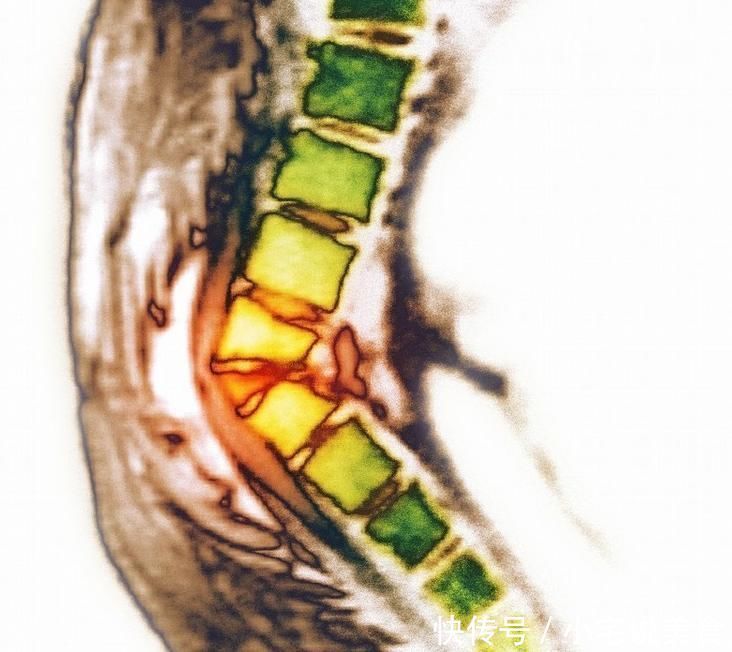

4、呼吸功能下降

當(dāng)患有骨質(zhì)疏松之后,患者身體的胸、腰椎處容易出現(xiàn)壓縮性骨折。主要指的是脊椎部有后彎和胸廓變得畸形的現(xiàn)象,當(dāng)患者出現(xiàn)這種現(xiàn)象時其體內(nèi)的肺活量和大的換氣量會有所減少,因此時常就會出現(xiàn)胸悶,氣短,甚至呼吸困難的癥狀。